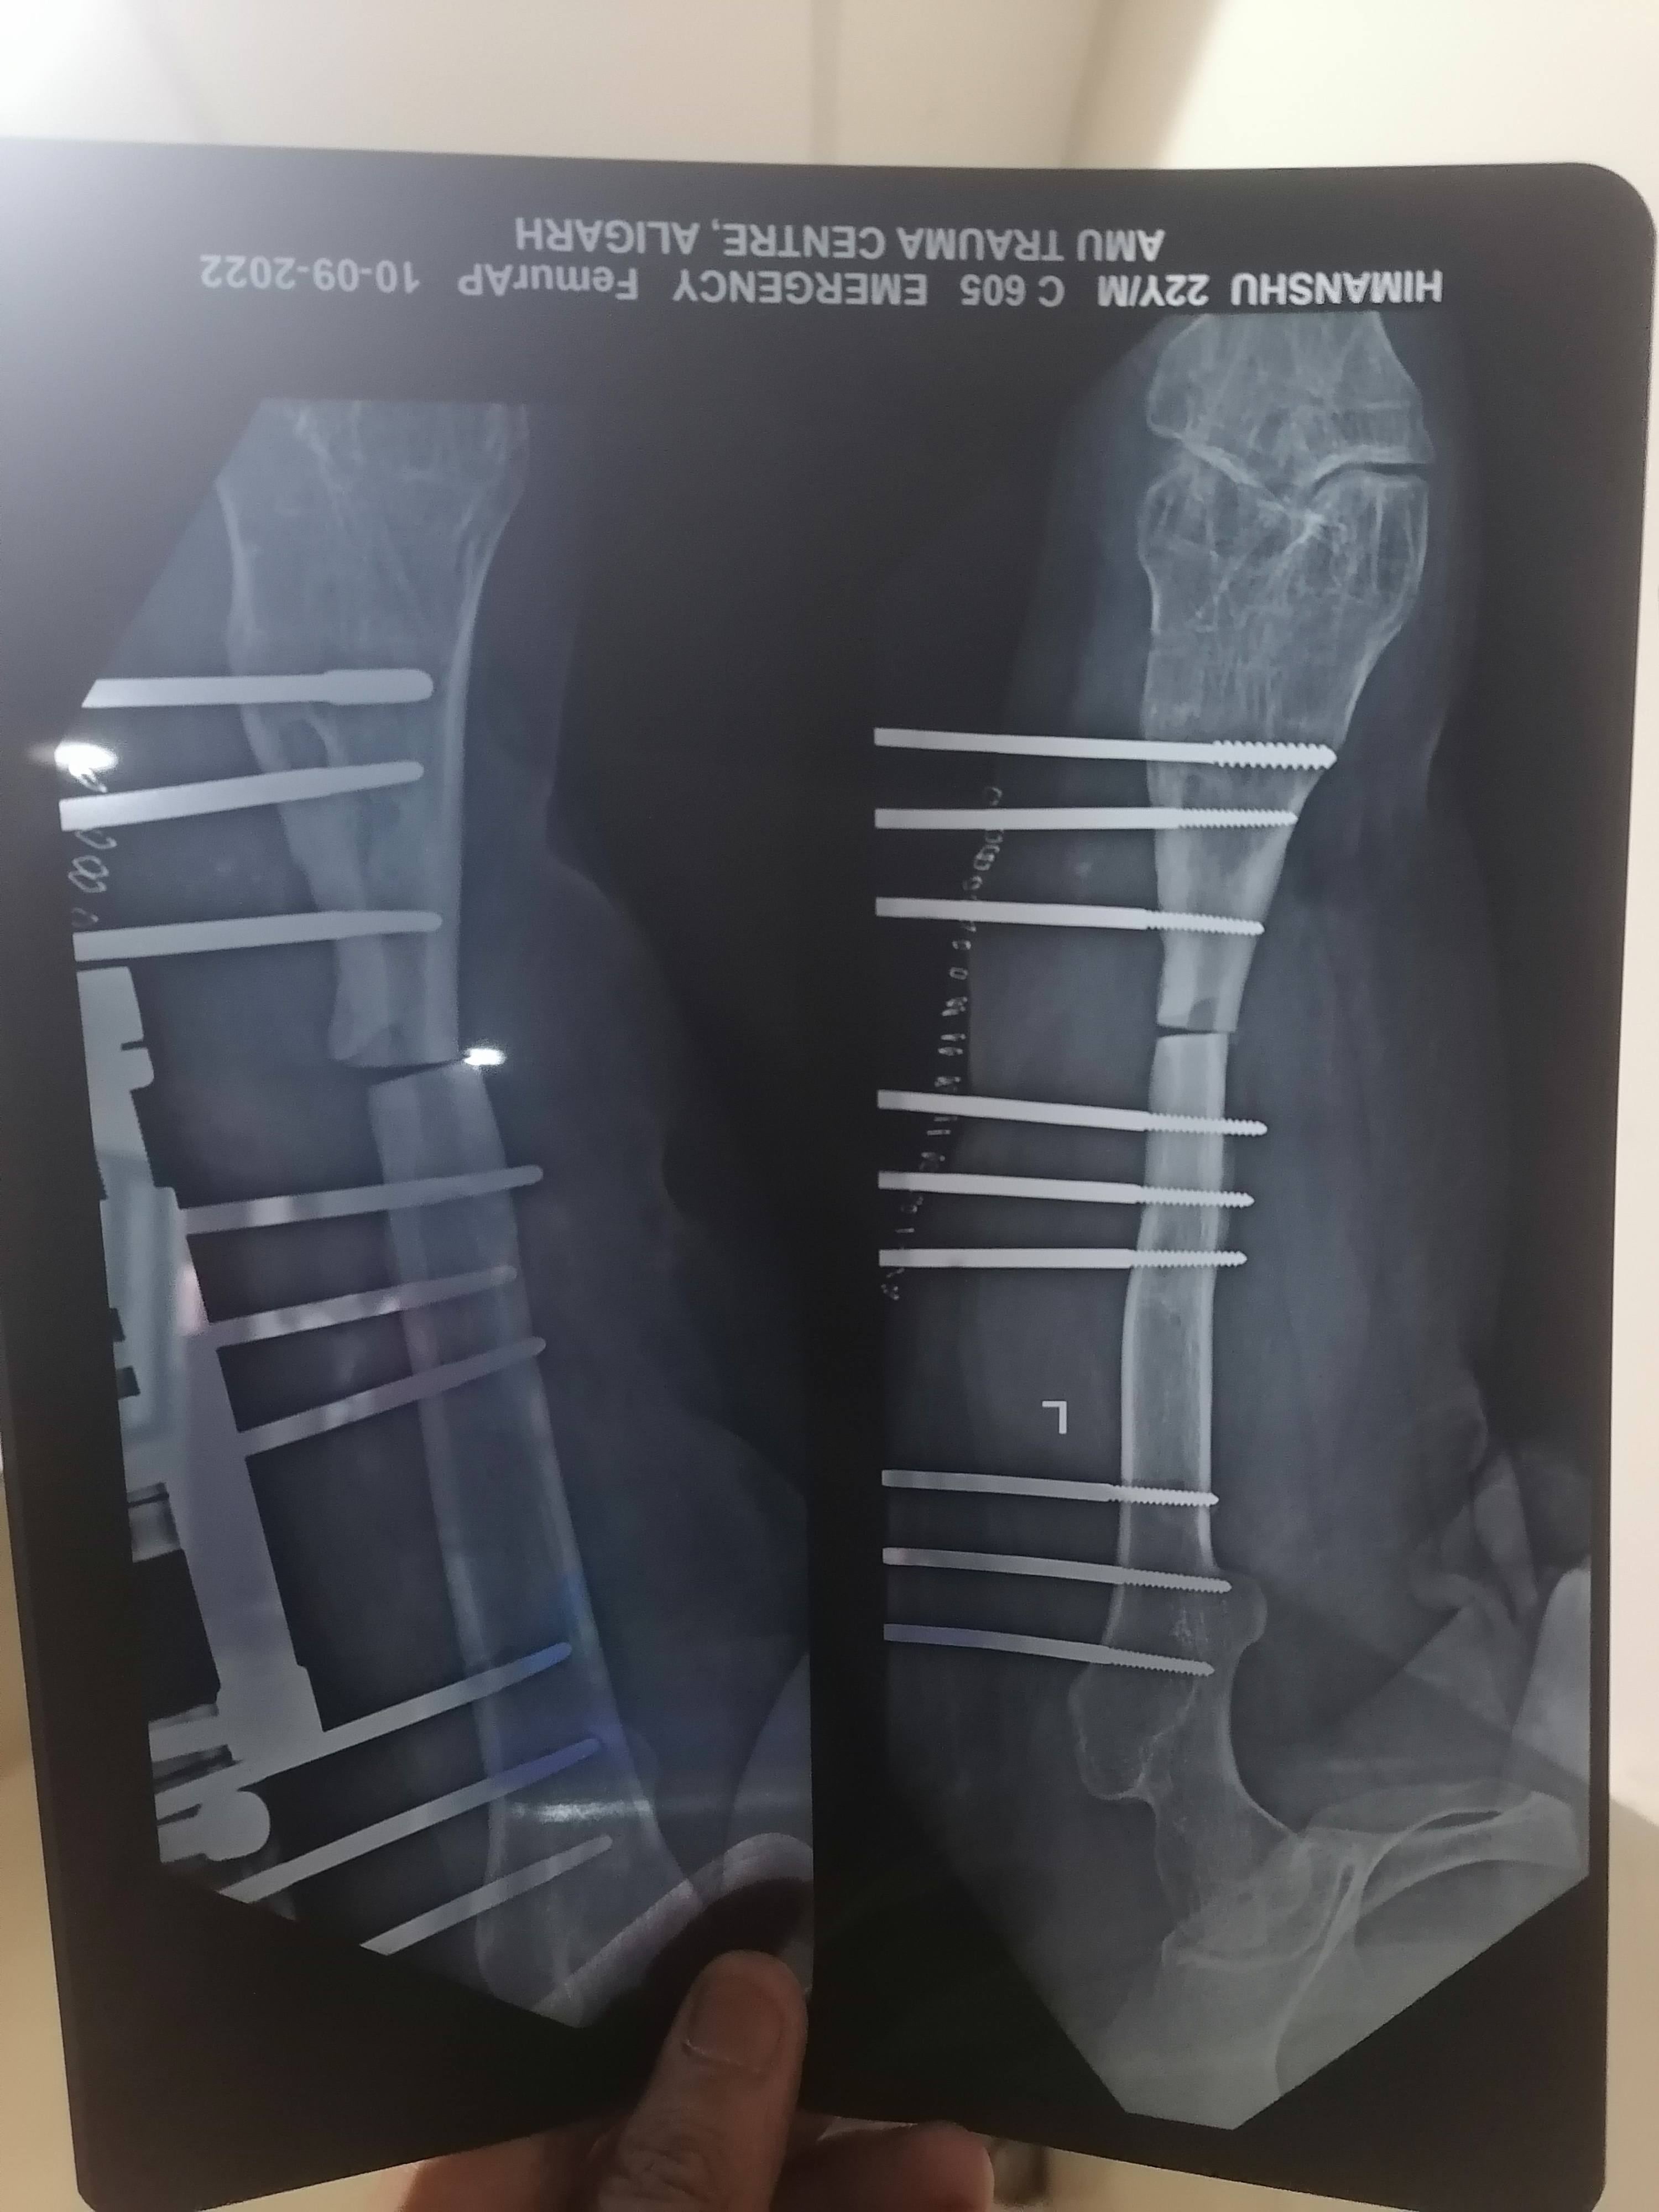

हिमांशु शर्मा

सर मेरे पैर में चोट लगने के कारण 7 साल से हड्डी में पस पड़ गया था फिर सर हड्डी टूट गई और उसमें अब ऑपरेशन कर के गली हुई हड्डी काट के LRS  लगा दिया 3 महीने हो गये पर सर पस बन्द नही है और हड्डी भी गली हुई नही है अब और सर हड्डी जुड़ी नही है और अब 7हप्ते पहले भी सफाई कर दी फिर भी पस आ रहा हैं थोड़ा